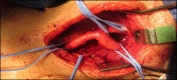

Abstract: A carotid body tumor is a rare neoplasm, generally benign, that predominantly affects people between their fourth and fifth decades of life. It manifests as a pulsatile and generally painless cervical mass with firm consistency, located below the angle of the jaw. It can progress to the extent that it causes localized pain, dysphagia, hiccups, hoarseness and hypersensitive carotid body syndrome. This article reports the cases of two female patients diagnosed with this tumor who were treated surgically. The first was treated with block resection of the tumor, while the second patient, who had an early stage tumor, was treated with subadventitial resection of the lesion.

O tumor de corpo carotídeo é uma neoplasia rara, geralmente benigna, que acomete, sobretudo, indivíduos entre a quarta e a quinta décadas de vida. Manifesta-se pela presença de massa cervical consistente localizada abaixo do ângulo da mandíbula, pulsátil e comumente indolor. Pode evoluir para dor local, disfagia, soluços, rouquidão e síndrome do corpo carotídeo hipersensível. Este artigo relata os casos de duas pacientes diagnosticadas com essa neoplasia e submetidas ao tratamento cirúrgico. A primeira foi submetida a uma ressecção em bloco do tumor, enquanto a segunda, com estadiamento mais precoce, foi tratada com uma ressecção subadventicial da lesão.